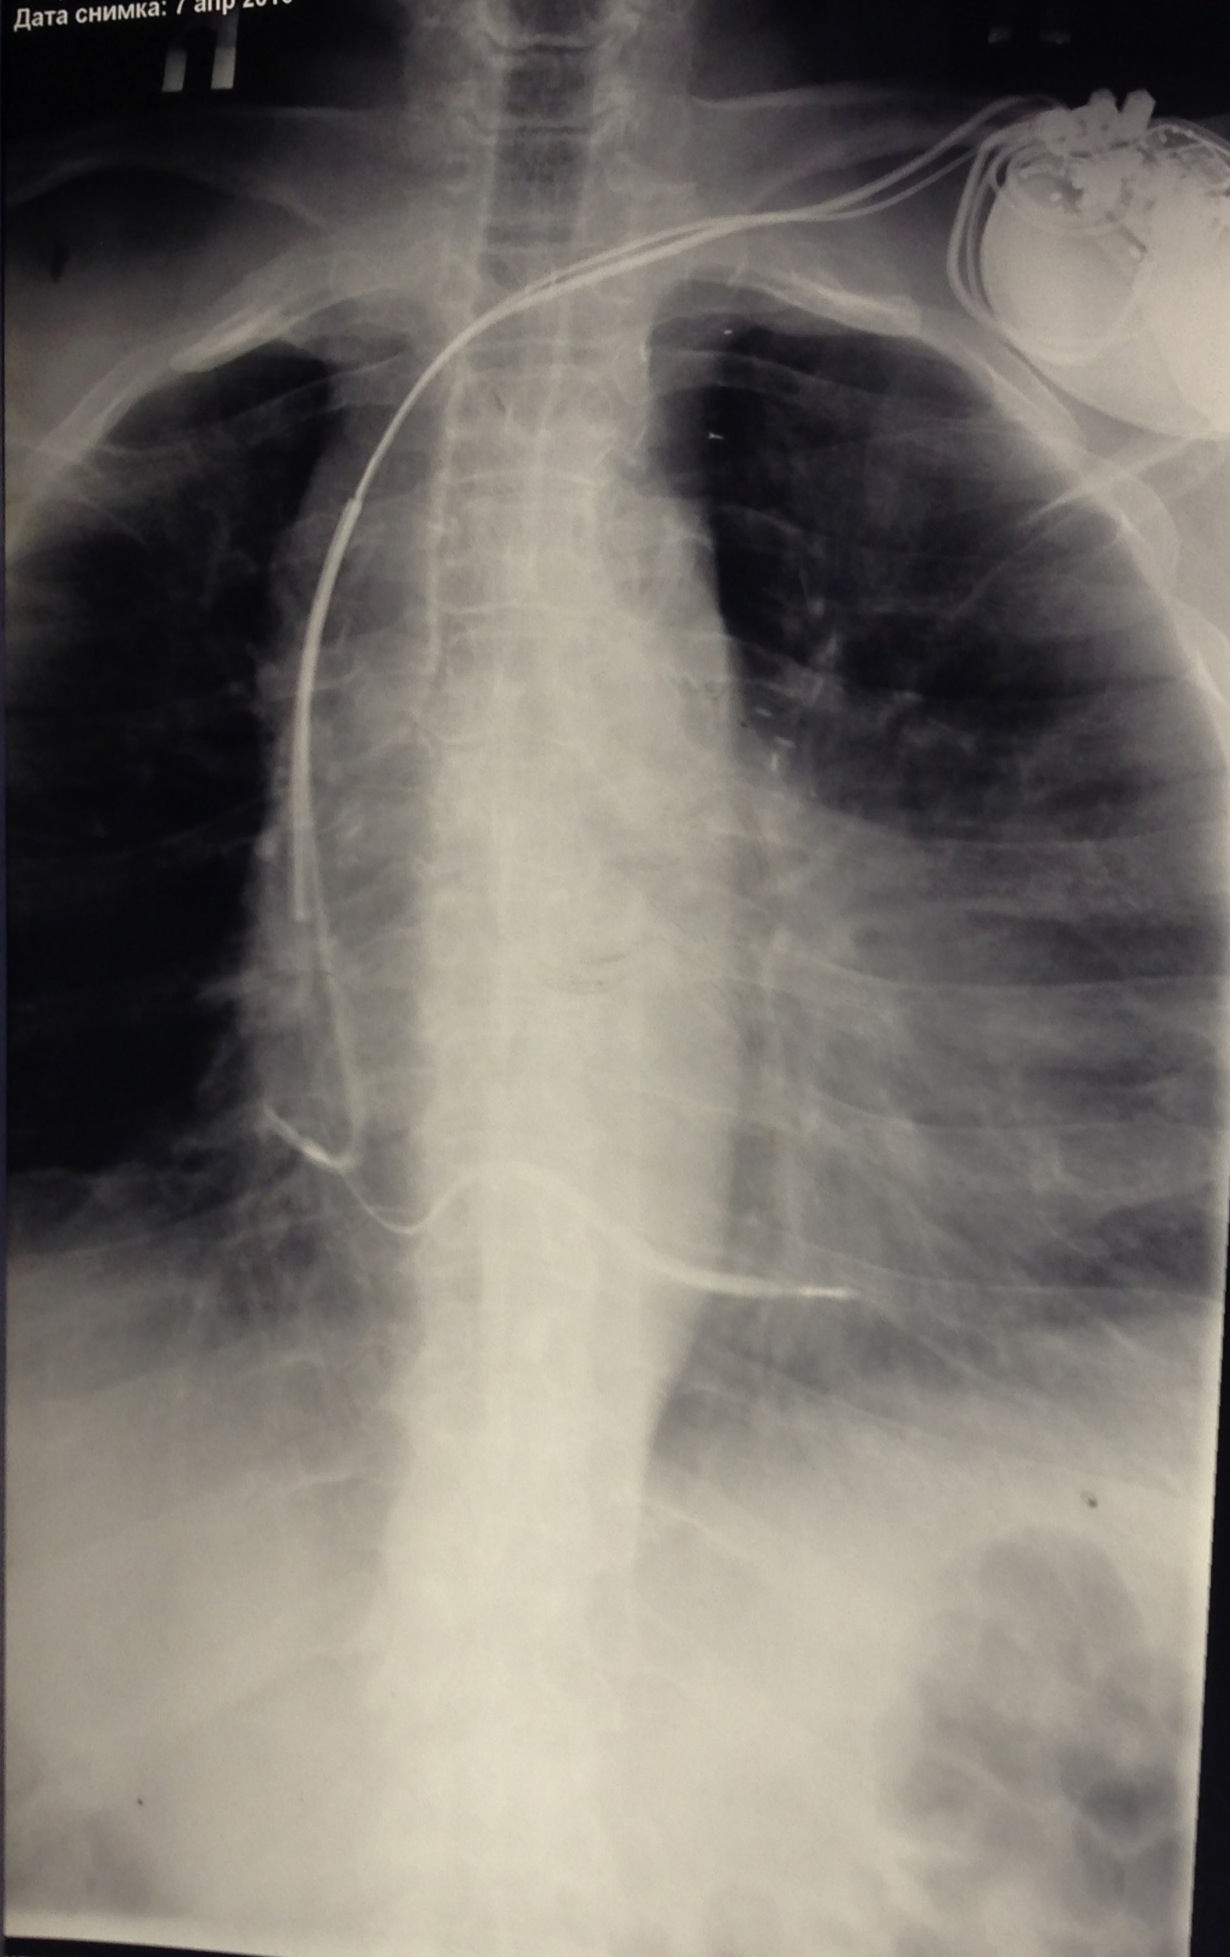

Один желудочковый электрод подключен, другой нет.

DDD+ ICD. Все на месте

1-.jpg

1-.jpg [ 323.1 KiB | Просмотров: 16662 ]